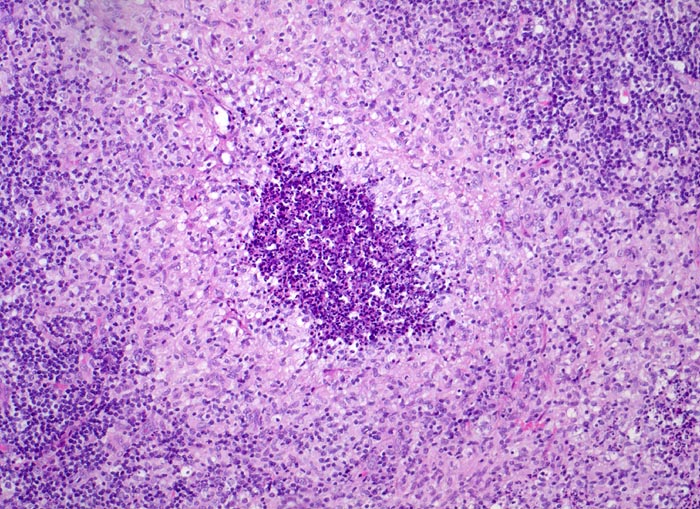

In der mittleren Dermis bilden sich Nekroseareale, welche von palisadierenden Histiozyten, mehrkernigen Riesenzellen und eosinophilen Granulozyten demarkiert werden. Die regionären Lymphknoten zeigen ebenfalls eine retikulozytär abszedierende Entzündung. Diese ist jedoch nicht spezifisch. Sie kommt auch vor bei Yersiniose, atypischer Mykobakteriose, Sporotrichose, Tularämie, Tumoren, Lymphogranuloma venereum und Coccidiomykose.